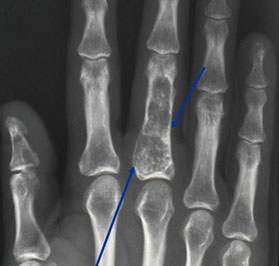

Enchondroma

MC form of chondroma (vs juxtacortical chondroma on bone surface); Rare (1% of all) benign bone tumors affecting the hands and feet (65%), and intramedullary metaphysis of long bones (25%) in younger pts (10-30 yo), presenting c pain and swelling

- grossly are usually <3 cm and gray blue and translucent and well-circumscribed nodules of b9 chondrocytes, that can infarct and calcify

Imaging: well-demarcated purely lytic popcorn-like calcifications (stippled radiolucent defects) and ring-calcifications (formed as part of endochondral ossification) oriented parallel to long axis

Micro: pseudolobules of cellular myxoid and cartilagenous tissue broken up by lines of connective tissue filled c vessels, mononuclear cells and MNGCs

- periphery shows dense spindle cell population (stellate cells in myxoid stroma c microcysts)

- 1 chondrocyte per lacuna

- centers of the lobules have immature cartilage c round chondrocytes that may be hyperchromatic and binucleated, but shouldn't have mits

- assess nuclear atypia at 20x by looking for vesicular chromatin, macronucleoli, and irregular nuclear membranes

-- can have some degree of atypia and inc cellularity, but should not have viable lamellar bone of Haversian canal infilatration (dx chondrosarcoma)

Assoc c Olliers (multiple enchondromatosis) and Maffucci's syndrome (spindle cell hemangioendothelioma)

Genes: Heterozygous mutation of IDH1 and IDH2, encoding isocitrate dehydrogenase, producing the oncometabolyte 2-hydroxyglutarate, which diffuses into neighboring cells and causes oncogenic epigenetic changes (transformation by association)

Medullary margins are scalloped and sclerotic (suggesting benign lesion); peripheral margin can be expanded by secondary aneurysmal transformation

Tx: en-bloc excision

Px 20% recurrence rate

Enchondroma of proximal phalynx

Enchondroma of femur